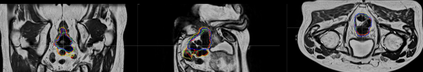

Direct automatic segmentation of objects from 3D medical imaging, such as magnetic resonance (MR) imaging, is challenging as it often involves accurately identifying a number of individual objects with complex geometries within a large volume under investigation. To address these challenges, most deep learning approaches typically enhance their learning capability by substantially increasing the complexity or the number of trainable parameters within their models. Consequently, these models generally require long inference time on standard workstations operating clinical MR systems and are restricted to high-performance computing hardware due to their large memory requirement. Further, to fit 3D dataset through these large models using limited computer memory, trade-off techniques such as patch-wise training are often used which sacrifice the fine-scale geometric information from input images which could be clinically significant for diagnostic purposes. To address these challenges, we present a compact convolutional neural network with a shallow memory footprint to efficiently reduce the number of model parameters required for state-of-art performance. This is critical for practical employment as most clinical environments only have low-end hardware with limited computing power and memory. The proposed network can maintain data integrity by directly processing large full-size 3D input volumes with no patches required and significantly reduces the computational time required for both training and inference. We also propose a novel loss function with extra shape constraint to improve the accuracy for imbalanced classes in 3D MR images.

翻译:3D医学成像的物体,如磁共振成像(MR)成像的直接自动分离,具有挑战性,因为往往需要精确地确定大量调查中大量存在复杂地理不对称的单个物体。为了应对这些挑战,大多数深层学习方法通常会大大提高其模型内可训练参数的复杂性或数量,从而提高其学习能力。因此,这些模型一般需要在运行临床MR系统的标准工作站上花很长的推断时间,并限于高性能的计算机硬件,因为它们的记忆要求很大。此外,要在这些大型模型中安装3D数据集,还要利用有限的计算机记忆,经常使用交换技术,例如补对称培训等,以牺牲从对诊断目的具有临床重要性的投入图像中获得的精细比例的几何地理信息。为了应对这些挑战,我们提出一个具有浅度记忆足迹的银色网络,以有效减少为状态性能所需的模型参数数量。这对于实际就业至关重要,因为大多数临床环境只有低端硬件,计算机功能和记忆有限。拟议的网络可以通过直接处理全尺寸三维化技术来保持数据的完整性,直接处理全尺寸的全尺寸三维的图像,从而大幅改进所需的超度变压的磁度计算。